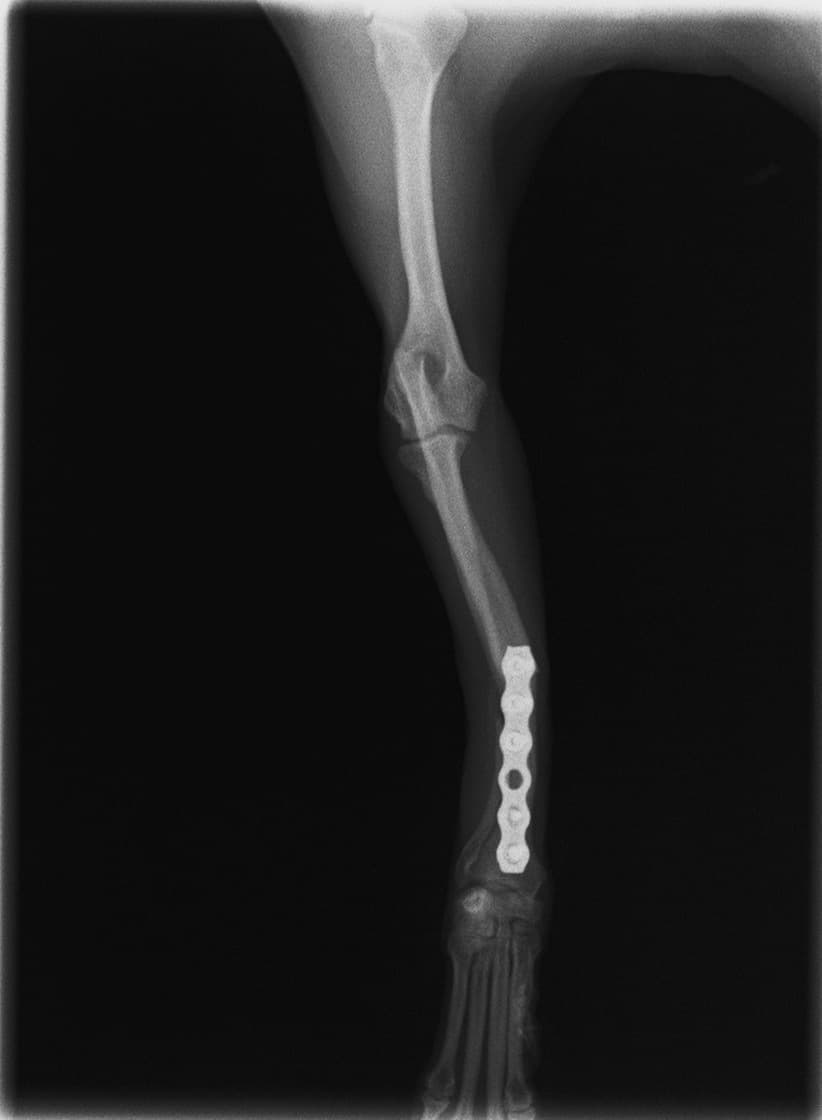

トイプードル 右遠位橈尺骨短斜骨折のALPSによる内固定

Locking Compression Plate

LCPは、スクリュー(ネジ)とプレート(金属の板)をロックする特殊な構造により骨折部位を固定する新しい世代のプレートシステムです。ひとつのホールでロッキングスクリューとスタンダードスクリューの使用を選択できるユニークな構造をしているため、骨折断端間の圧迫を目的とした従来型プレート固定法に加え、高い角度安定性を有するロッキングスクリューを用いた固定法の選択が可能です。従来のプレートシステムでは困難だった部分の骨折や癒合不全の症例に高い治療効果をもたらします。